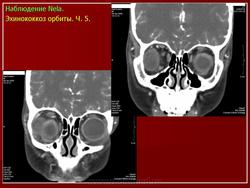

Клинически рост паразита проявляется медленным увеличением экзофтальма (в течение 5—8 лет). Общие патологические изменения, как правило, отсутствуют, в течение длительного периода времени не развивается даже столь характерная для паразитарных заболеваний эозинофилия. Чувство напряжения в орбите появляется, когда пузырь достигает больших размеров и сильно сдавливает мягкие ткани орбиты и глазное яблоко. Из диагностических методов исследования наиболее информативны ультразвуковое сканирование и компьютерная томография, с помощью которых удается четко визуализировать тень кисты и ее капсулу. Лечение хирургическое — орбитотомия и извлечение кисты, желательно без нарушения капсулы.